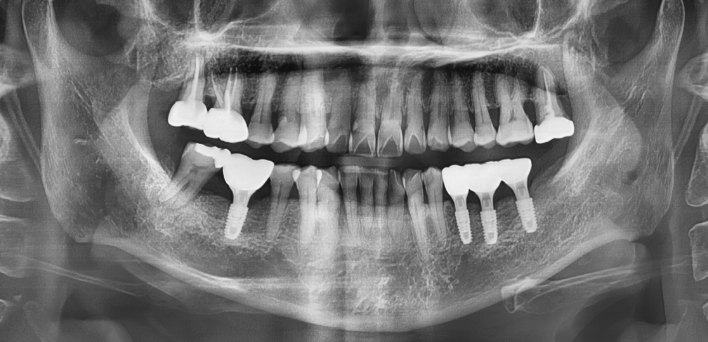

임플란트 : 손 ** 님 (50대)

After After

2020.02.30

환자 특징01무치악 상태

환자 특징02수년간 무치악으로 지내심

임플란트가 불가능할것이라

생각하고 내원

위, 아래 6개씩 식립

디지털 풀아치 임플란트

더서울치과의원은 다수의 임플란트 수술 경험을 토대로 정확한 디지털 기반 진단,

환자에게 가장 적합한 수술 방법으로 내 치아처럼 오래 사용하는 임플란트를 식립합니다.